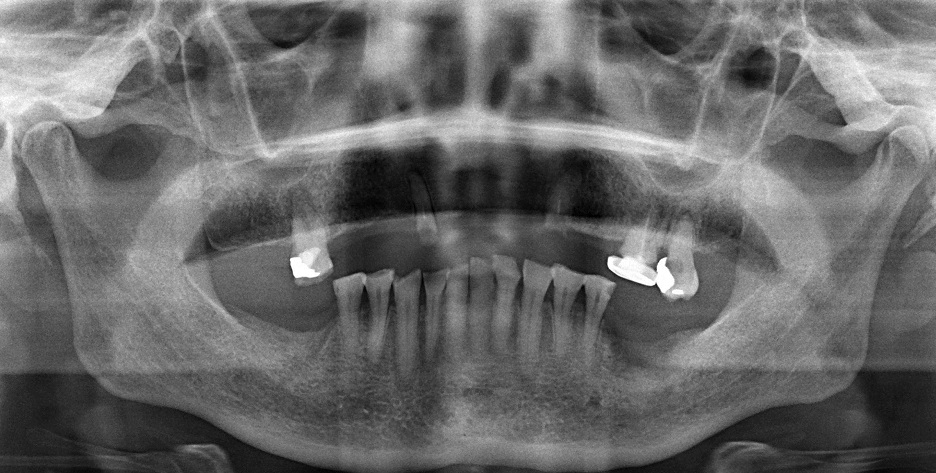

拍完CT后的口腔

通过三维重建与可视化处理清楚显示种植区颌骨的牙槽骨高度和宽度、骨质密度、颏孔位置、下牙槽神经管走向、鼻腔底和上颌窦底的位置和形态等;